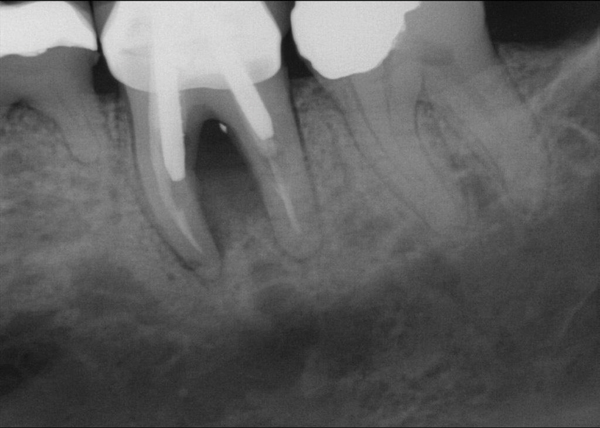

Fig 20. (Case 4) Radiograph of tooth No. 30, which had a hopeless prognosis.

Figure 20

Fig 21. Radiograph of extraction socket. Buccal plate was two-thirds resorbed.

Figure 21